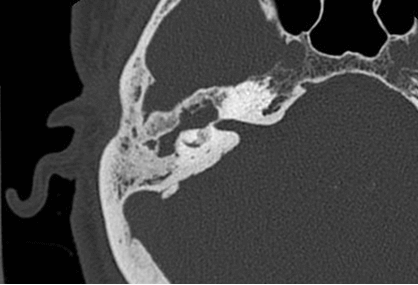

Answer: This cochlea is ossified; the cochlea is normally fluid filled and therefore low density on CT.

(A) axial non contrast CT of the temporal bone demonstrates hyperdensity within the right cochlea (red arrow) consistent with ossification. Compare to the mixed soft tissue/fluid density of the adjacent internal auditory canal (IAC, blue arrow) and the cochlea on the opposite side marked in blue in (B) and (C).